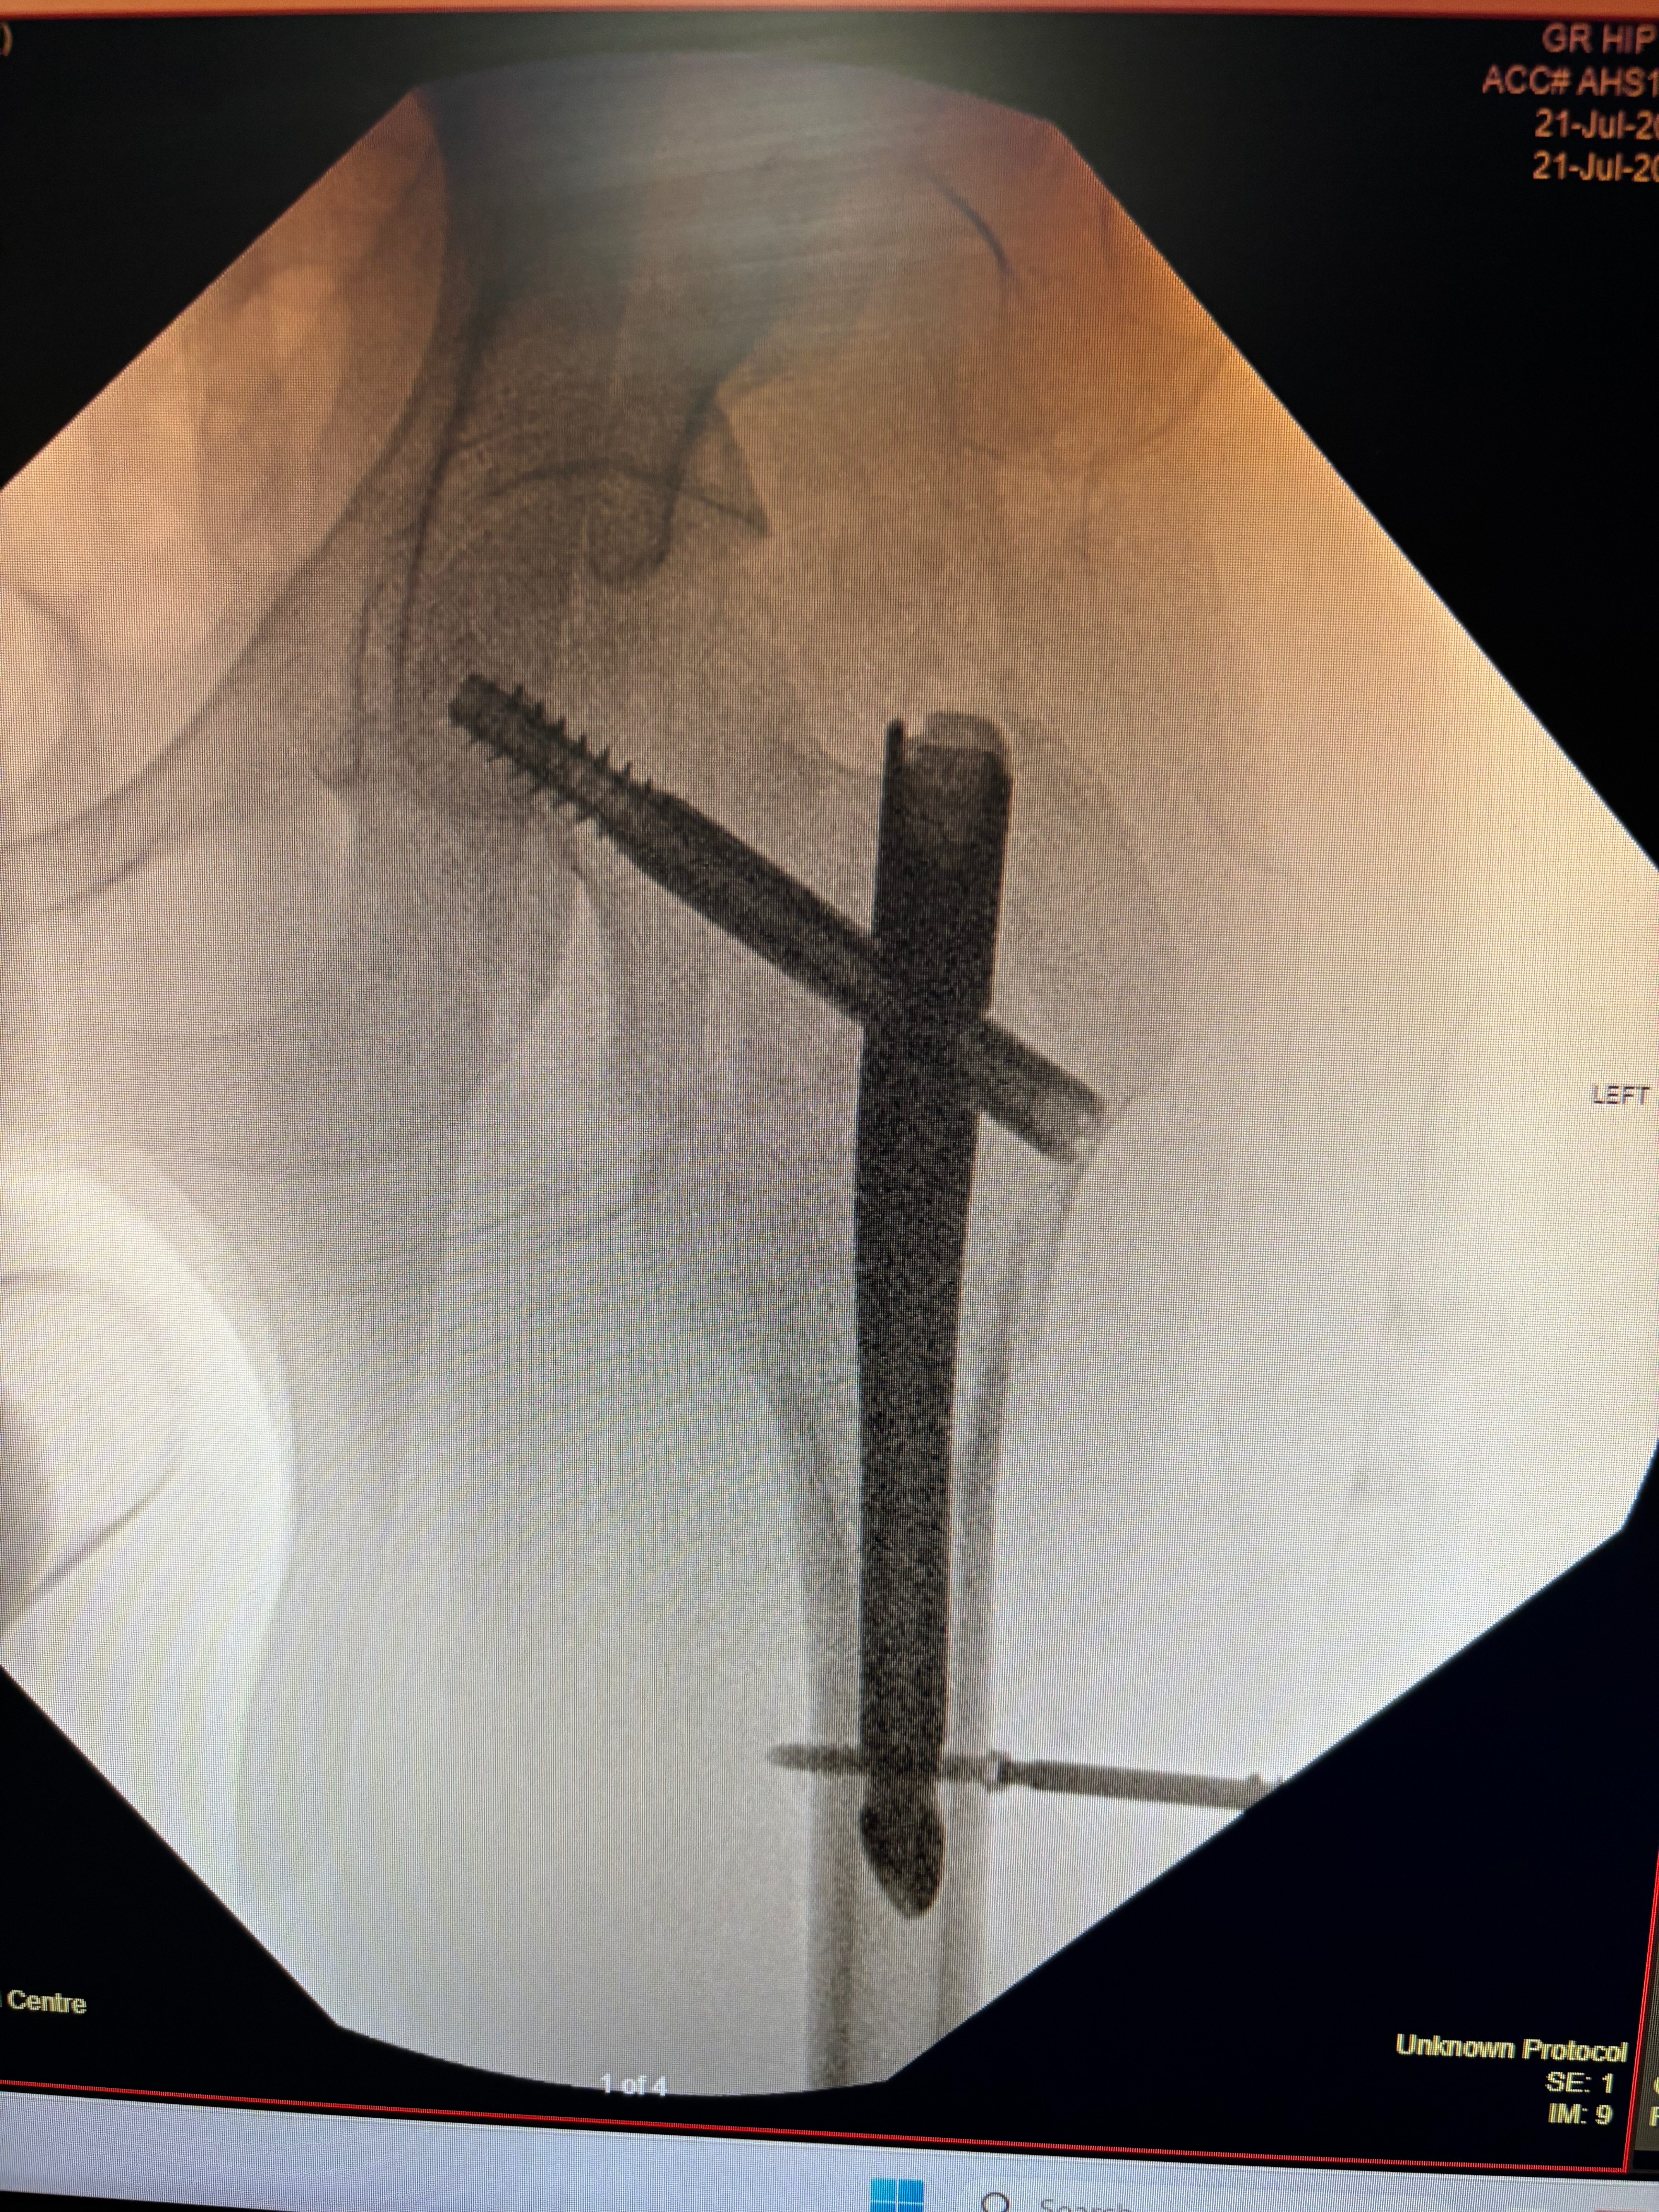

The danger of riding a scooter… Dylan was riding a scooter to work and hit a pothole catapulting him into the air. He landed on his left side and broke his wrist (distal radiul fracture) and his hip. After a lot of pain and surgery on his wrist and hip (intramedullary nailing) Google it I had to, basically a metal rod in his femur and a bolt holding the hip joint in place.